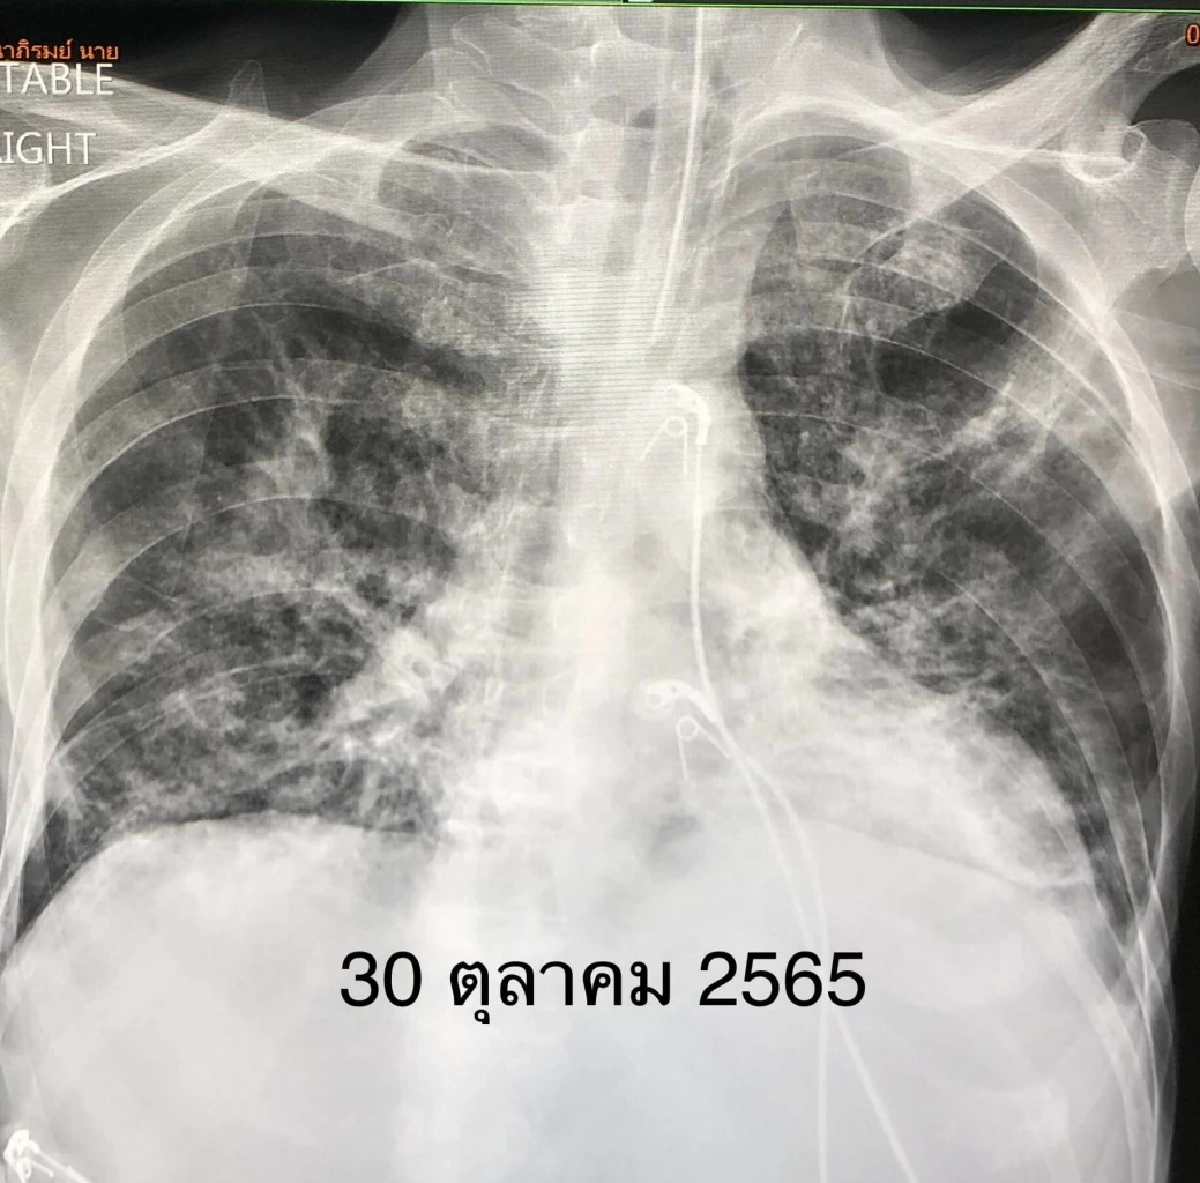

ผู้ป่วยชายอายุ 53 ปี เป็น มะเร็งเม็ดเลือดขาว 3 ปี ฉีดวัคซีนป้องกัน โรคโควิด แอสตราเซเนกา 2 เข็ม และไฟเซอร์ 1 เข็ม เริ่มมีไข้สูง ไอ เจ็บคอ 3 วัน ตรวจ ATK ให้ผลบวก เหนื่อยมาก เข้าโรงพยาบาลวันที่ 28 ตุลาคม 2565 ระดับออกซิเจนที่ปลายนิ้วต่ำมาก 80% เอกซเรย์ปอดมีฝ้าขาวทั้ง 2 ข้าง ตรวจรหัสพันธุกรรม 22 สายพันธุ์ พบ ไวรัสโควิด RT-PCR SARS-CoV-2 CT value 17.1 ไม่พบไวรัสตัวอื่น เข้าห้องไอซียู ให้ออกซิเจนชนิด high-flow nasal cannula (HFNC) ให้ ยาเรมเดซิเวียร์ และยาสเตียรอยด์ชนิดฉีดเข้าเส้นเลือดดำ

คนไข้ไม่ดีขึ้น เหนื่อยมากขึ้น เอกซเรย์ปอดแย่ลง ต้องใส่ท่อหายใจ และเครื่องช่วยหายใจ ความดันตำ่จนช็อกในวันที่ 30 ต.ค. 2565 ต้องให้ยาเพิ่มความดัน แต่หลังจากการรักษา คนไข้อาการดีขึ้นช้าๆ ความดันดีขึ้น ไข้ลง เหนื่อยลดลง ในที่สุดถอดเครื่องหายใจได้วันที่ 4 พ.ย. 2565 แต่ยังต้องใช้ออกซิเจนเสียบจมูก ได้ยาฉีด เรมเดซิเวียร์ และสเตียรอยด์ครบ 10 วัน